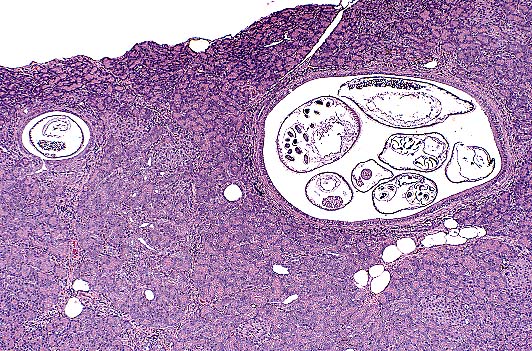

Case I -MK96-1677 (AFIP 2535991)

Signalment: Adult male Rhesus macaque (Macaca mulatta).

High-grade astrocytoma in the cerebrum of a rhesus monkey showing characteristic palisading of neoplastic cells along areas of necrosis. (HE, 40X, 54K)

History: This nonhuman primate stopped eating, became progressively blind and incoordinate, and pressed its head against the wall of its cage. Ophthalmic examination was inconclusive. Humane euthanasia was elected, and the animal was submitted for necropsy and histopathological evaluation.

Gross Pathology: The macaque was moderately dehydrated, poorly muscled, and had scant stores of body fat. Other gross necropsy findings were confined to the brain. The meninges covering the dorsal aspect of the cerebrum were diffusely congested. Effacing the cerebral cortex of the left occipital lobe, there was 3 x 2 x 2 cm, well demarcated, expansile mass. The mass was unencapsulated, friable, and tan with multifocal pale areas. There was cerebellar coning consistent with increased intracranial pressure

Contributor's Diagnosis and Comments: Cerebrum, left occipital lobe: Astrocytoma, high grade, Rhesus macaque.

Astrocytomas generally occur as soft tissue masses in the substance of the cerebral hemispheres, and produce a spectrum of clinical signs based on their exact location. The majority of astrocytomas are well-differentiated with a relatively uniform population of transformed astrocytes having oval nuclei, little heterochromatin and poorly defined cell borders. The tumors can be graded, but regardless of grade there is a background of astrocytic processes between neoplastic nuclei. Higher grade astrocytomas are characterized by increasing nuclear anaplasia, mitotic activity and vascular proliferation. In the adjacent parenchyma, endothelial cells may form glomeruloid proliferations within vascular lumina. These are prominent in high grade astrocytomas, and were present in this case. The highest grade astrocytomas are usually very cellular, and have a mixture of firm white areas, and softer yellow foci of necrosis. These latter features, especially the presence of necrosis, have given rise to the term glioblastoma multiforme. Immunohistochemistry performed by AFIP was positive for glial fibrillary acidic protein (GFAP) and negative for S100, synaptophysin, cytokeratin, and vimentin.

AFIP Diagnosis: Cerebrum: Astrocytoma, high grade (glioblastoma multiforme), Rhesus monkey (Macaca mulatta), non-human primate.

Conference Note: This case has classic features of glioblastoma multiforme, which is often simply called high grade astrocytoma. These features include high cellularity, pleomorphism, necrosis, subpial spread, cortical infiltration, necrosis surrounded by "pseudopalisades" and areas of glomerulus-like endothelial proliferation. Recent evidence suggests that vascular endothelial cell growth factor (VEGF) is secreted by malignant astrocytes perhaps in response to hypoxia.